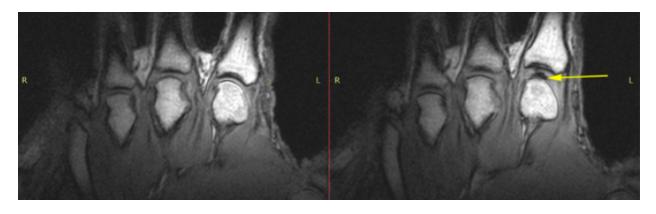

从 1948 年到 1998 年 ,已是医学博士的唐纳德把左手掰了至少 36500 次。

而 50 年后,他两只手的状态,无论是肉眼所见还是 X 光影像,并没有任何差别,都很健康。

图片来源:网络

掰手指 ≠ 关节炎,虽然,把这个结论拿来反驳妈妈早已来不及了。